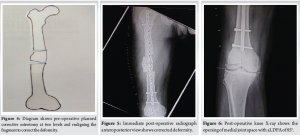

Post-operative radiograph demonstrates normal anatomical axis (Fig. 5), deformity corrected, and significant opening of medial joint space of right knee (Fig. 6).

The aLDFA measured was 85° (Fig. 6). In the lateral view, there was no deformity, and clinically assessed, there was no rotational component.

Clinically, the deformity was corrected and the patient was started on partial weight bearing on Post-operative day 2 and his main symptoms of medial side knee pain were significantly improved with a VAS score of 3 (Fig.7).

At the 6-month follow-up, the patient was walking full weight bearing with a mild limp, and there were no complaints of medial side knee pain, which was his main complaint preoperatively (Fig. 8).

The radiologically distal level osteotomy site was united, but the proximal level was not united, which might be the reason for his limp. The implant was in position without failure (Fig. 9).